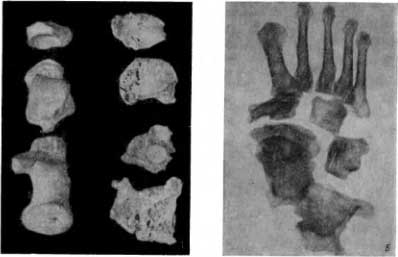

Заслуживают особого внимания обнаруженные нами проявления спинной сухотки (tabes dorsalis). Это заболевание, наблюдаемое лишь у людей, болевших сифилисом, возникает спустя много лет после заражения. Спинная сухотка представляет метасифилитическое системное перерождение задних столбов спинного мозга. Главным симптомом заболевания является неспособность конечностей выполнять координированные движения (атаксия), зависящая в основном от нарушения глубокой чувствительности. Обнаруживается полное отсутствие коленных рефлексов (а также целый ряд других симптомов, в частности со стороны глаз, позволяющих клинически поставить точный диагноз позднего нейролюэса).

Соответствующие анатомические изменения были найдены на костях женщины в Саркеле. В костях правой предплюсны этой, по-видимому, 50-летней женщины наблюдалось своеобразное поражение, которое невропатологи называют табической плоской стопой. Вследствие расслабления тонуса мышц и связок свод стопы уплощается. У данной женщины кости предплюсны — пяточная, таранная и ладьевидная — оказались как бы раздавленными, уплощенными и подвергшимися частичному остеолизу и патологическому перелому (рис. 39, А). Наибольшей деструкции подверглась пяточная кость; она представлена двумя столь деформированными фрагментами, что с трудом можно распознать, с какой костью мы имеем дело (рис. 39, А и Б). Таранная кость уменьшена в объеме; в ней наряду с деструктивными изменениями имеется реактивное костеобразование, в основном не несущее нагрузки (рис. 39, Б). Ладьевидная кость стопы резко уплощена и в то же время увеличена в длину и ширину; суставная поверхность на небольшом участке продырявлена.

Рис. 39. А — метасифилитическое поражение пяточной кости, таранной и ладьевидной костей, табическая артропатия; Б — табическая артропатия в рентгеновском изображении.

На мацерированных костях изменения, характерные для табической плоской стопы, представляют большую музейную (научную и учебную) ценность.